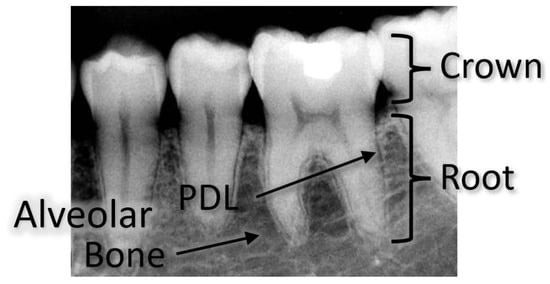

Figure 1.

Tooth relevant components under X-ray imaging.

Orthodontic tooth movement (OTM) is initiated and controlled by mechanical stimuli generated by forces applied on the crown of the tooth [1]. The forces are partially governed by the periodontal ligament (PDL), which connects the teeth to the surrounding alveolar bone and decreases the rigidity of the jaw [2]; thus, the stress–strain responses of teeth and the PDL to orthodontic loading are of importance (i.e., for better understanding and for improving orthodontic yield). OTM is governed by several factors, some of which are not completely known for each patient, such as the PDL properties (i.e., thickness, stiffness, etc.) [3]. The applied forces, if not sufficiently known [4], might result in clinical side effects, such as uncontrolled tipping of the tooth or excessive stresses on the root apex that may result in root resorption. Therefore, revealing the stress–strain responses of the teeth, alveolar bone and PDL to orthodontic loading is of great importance in order to apply optimal forces during treatment. It may also be beneficial for studies of new orthodontic techniques, such as clear aligners [5]. Moreover, recent studies, such as [6], which suggest the use of machine learning in orthodontics may benefit from an efficient OTM model, such as the one suggested here.

The alveolar bone’s inner structure consists of an interconnected network of trabecular rods and plates, while its outer shell presents with the more compact structure of a cortical bone [7].